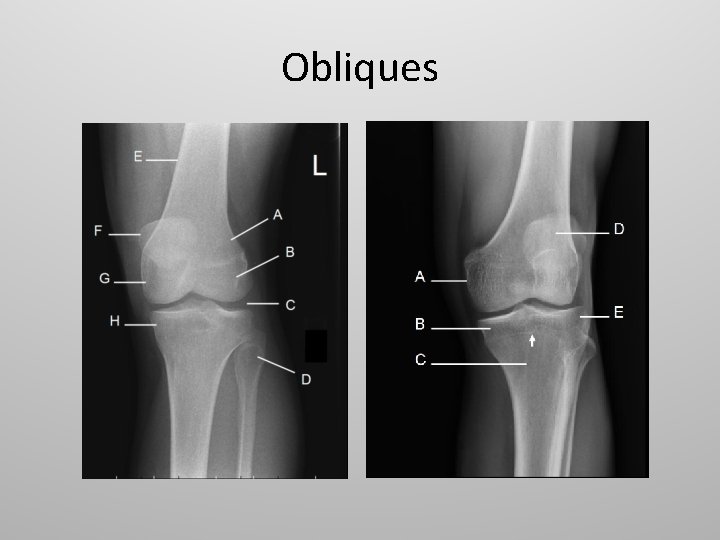

Obliques